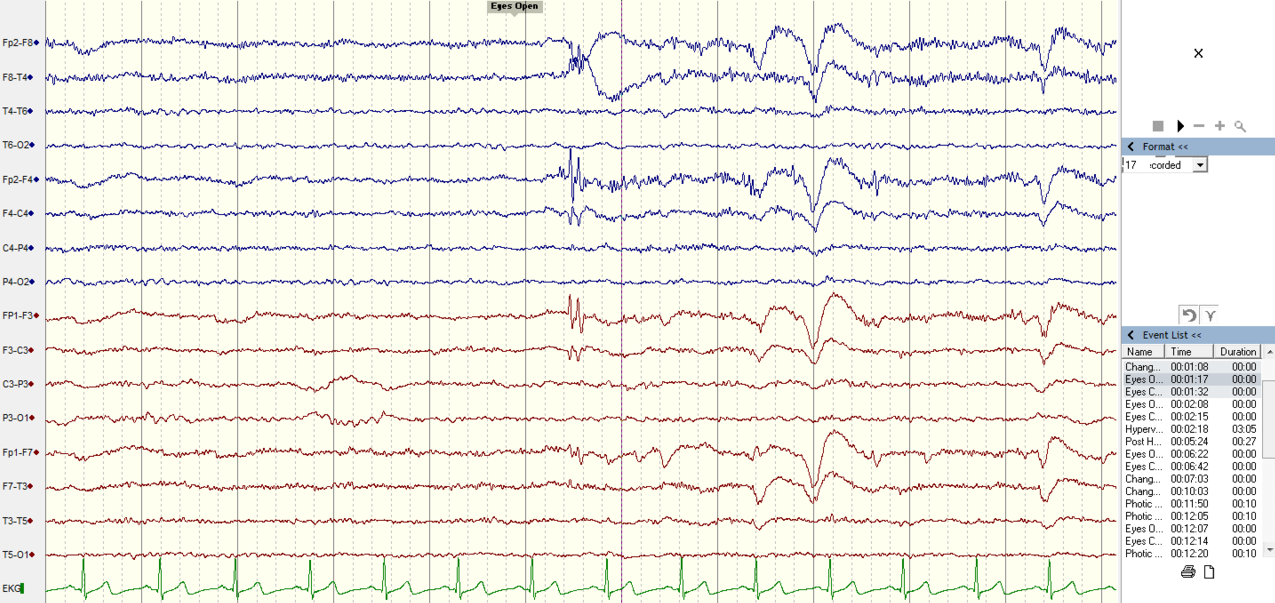

Электрическая активность мозга измеряется с помощью электроэнцефалограммы. Пример ЭЭГ человека в состоянии покоя с открытыми глазами